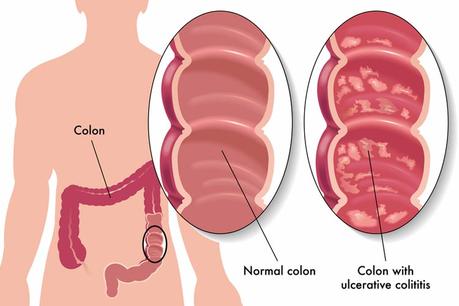

Ulcerative colitis (UC) is a condition in which, there is inflammation and ulcers in the colon and the rectum part of the intestine. This is also known as Inflammatory Bowel Disease (IBD). This disease causes inflammation and sores (ulcers) in the digestive tract. UC affects mostly the lining of the large intestine (colon) and rectum. The major symptoms of Ulcerative colitis are pain in the abdomen and diarrhea mixed with blood. Fever, weight loss, and anemia can also occur in this disease.

There are different types of Ulcerative colitis are depending upon the location and severity of the disease, these types are mentioned below: –